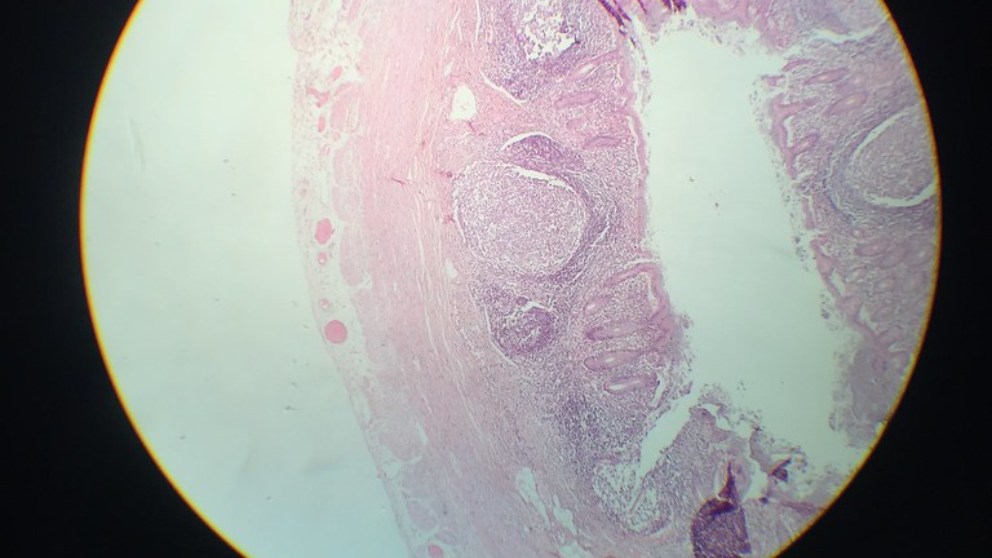

Durante años el apéndice ha sido una especie de misterio para los científicos, pero varios estudios han podido concluir al fin, a qué corresponde exactamente y cuál es su función, más allá de provocar la conocida apendicitis. Qué es el apéndice El apéndice es un tubo delgado de aproximadamente 10 centímetros de longitud que forma…